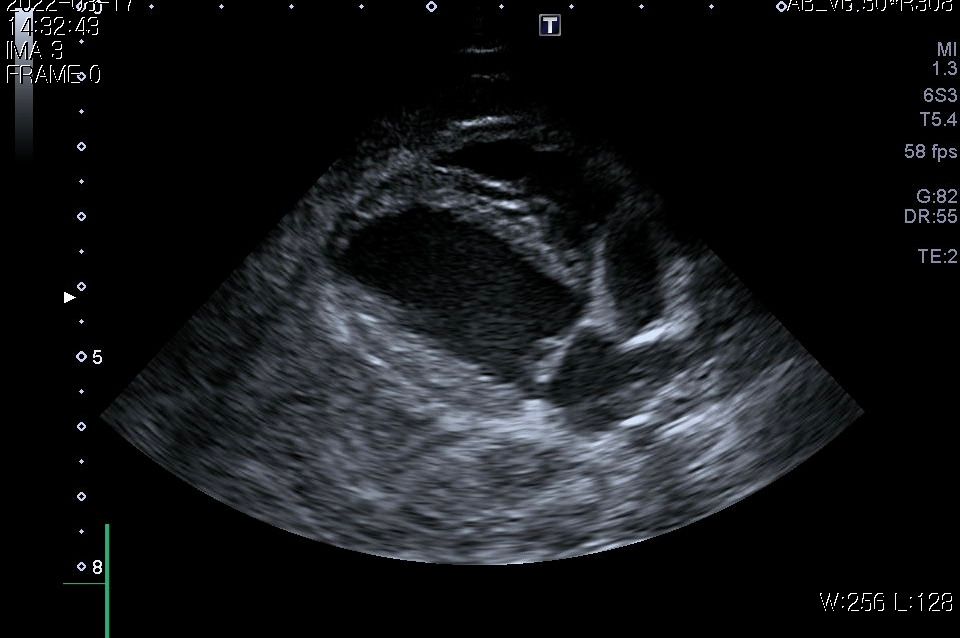

첨부해주신 사진만을 기초로 볼때 폐종양인 경우 좌측 폐전엽부의 종양이, 폐종양이 아닌 경우 종격동내의 종양 특히 흉선종양의 가능성이 높아 보입니다.

이 두가지 종양의 가능성이 사실 가장 높은 상태에서 CT 촬영을 해보아야 하는 이유는

폐종양의 경우 수술로 적출하는것이 비교적 수월하고 수술 이후 어느 정도 절제 하느냐에 따라 정상 생활까지 가능한 상태가 될 수 있기 때문입니다.

물론 폐 종양이 좌측 폐 전엽의 앞쪽 부분에 국한하여 있을 때만을 이야기 하는것으로

만약 좌측 폐전엽의 뒤쪽 부분까지 적출해야 하는 상태의 종양인 경우 수술 이후 호흡 부전이 잘 오고 산소처치를 계속 받으면서 살아야 할 가능성도 고려해야 합니다.

좌측 폐는 산소 교환 능력의 40% 정도를 차지하고 폐엽 절제술 후 산소 교환능에 영향을 주는 기준점이 40% 폐엽이니까요.

또한 흉선종인 경우 이정도 크기로 증가하는 경우에는 대부분 adenocarcinoma인 경우가 많고 그런 양상인 경우 혈관이나 미주신경 침습등의 가능성이 높아 수술불가 판정이 나올 수 있습니다.